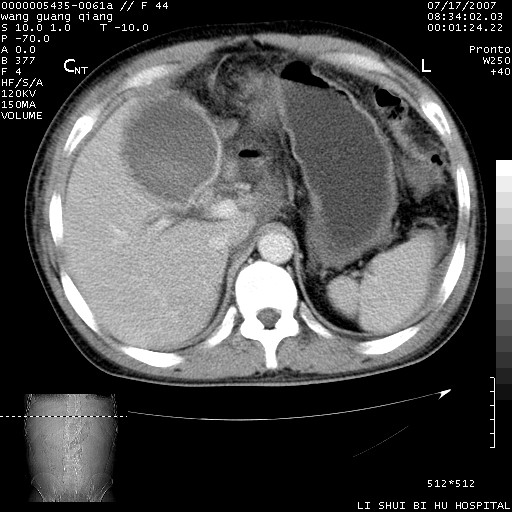

以下是引用dyqct在2007-7-18 10:46:00的发言:[br]胆囊明显增大,壁增厚,明显强化;后下方见大片高密度区,ct值68hu,无强化,周围见多数条纹状高密度影,边界不清。双膈下间隙、肝肾隐窝见带状及片状低密度区。[br]右侧胸壁后缘亦见新月形水样密度区。[br]考虑:1、急性胆囊炎伴周围出血;[br] 2、少量腹水、右侧少量胸腔积液。[br][br][本贴已被 dyqct 于 2007-7-18 10:48:47 修改过]